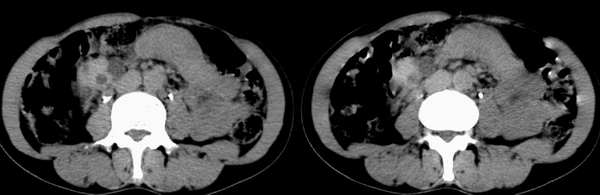

女性, 40岁。 10年前曾因腰痛在外院诊断双侧多囊肾并右肾多发结石(有静脉肾盂造影及b超报告,但没能见到影像图片)并行碎石处理且有排石史,后来一直无明显异常。但近2个月来自觉肝区饱满、右侧膈肌上抬,并进行性加重;血尿常规及淀粉酶阴性,血压正常。

平扫

右肾体积增大,形态失常,其内可见多发低密度影,增强后动脉期病灶实质明显强化,低密度区未见强化,静脉期病灶呈等密度,考虑右肾癌,左肾多发囊肿,多囊胰

右肾体积增大,形态失常,其内可见多发低密度影,增强后动脉期病灶实质明显强化,低密度区未见强化,静脉期病灶呈等密度.